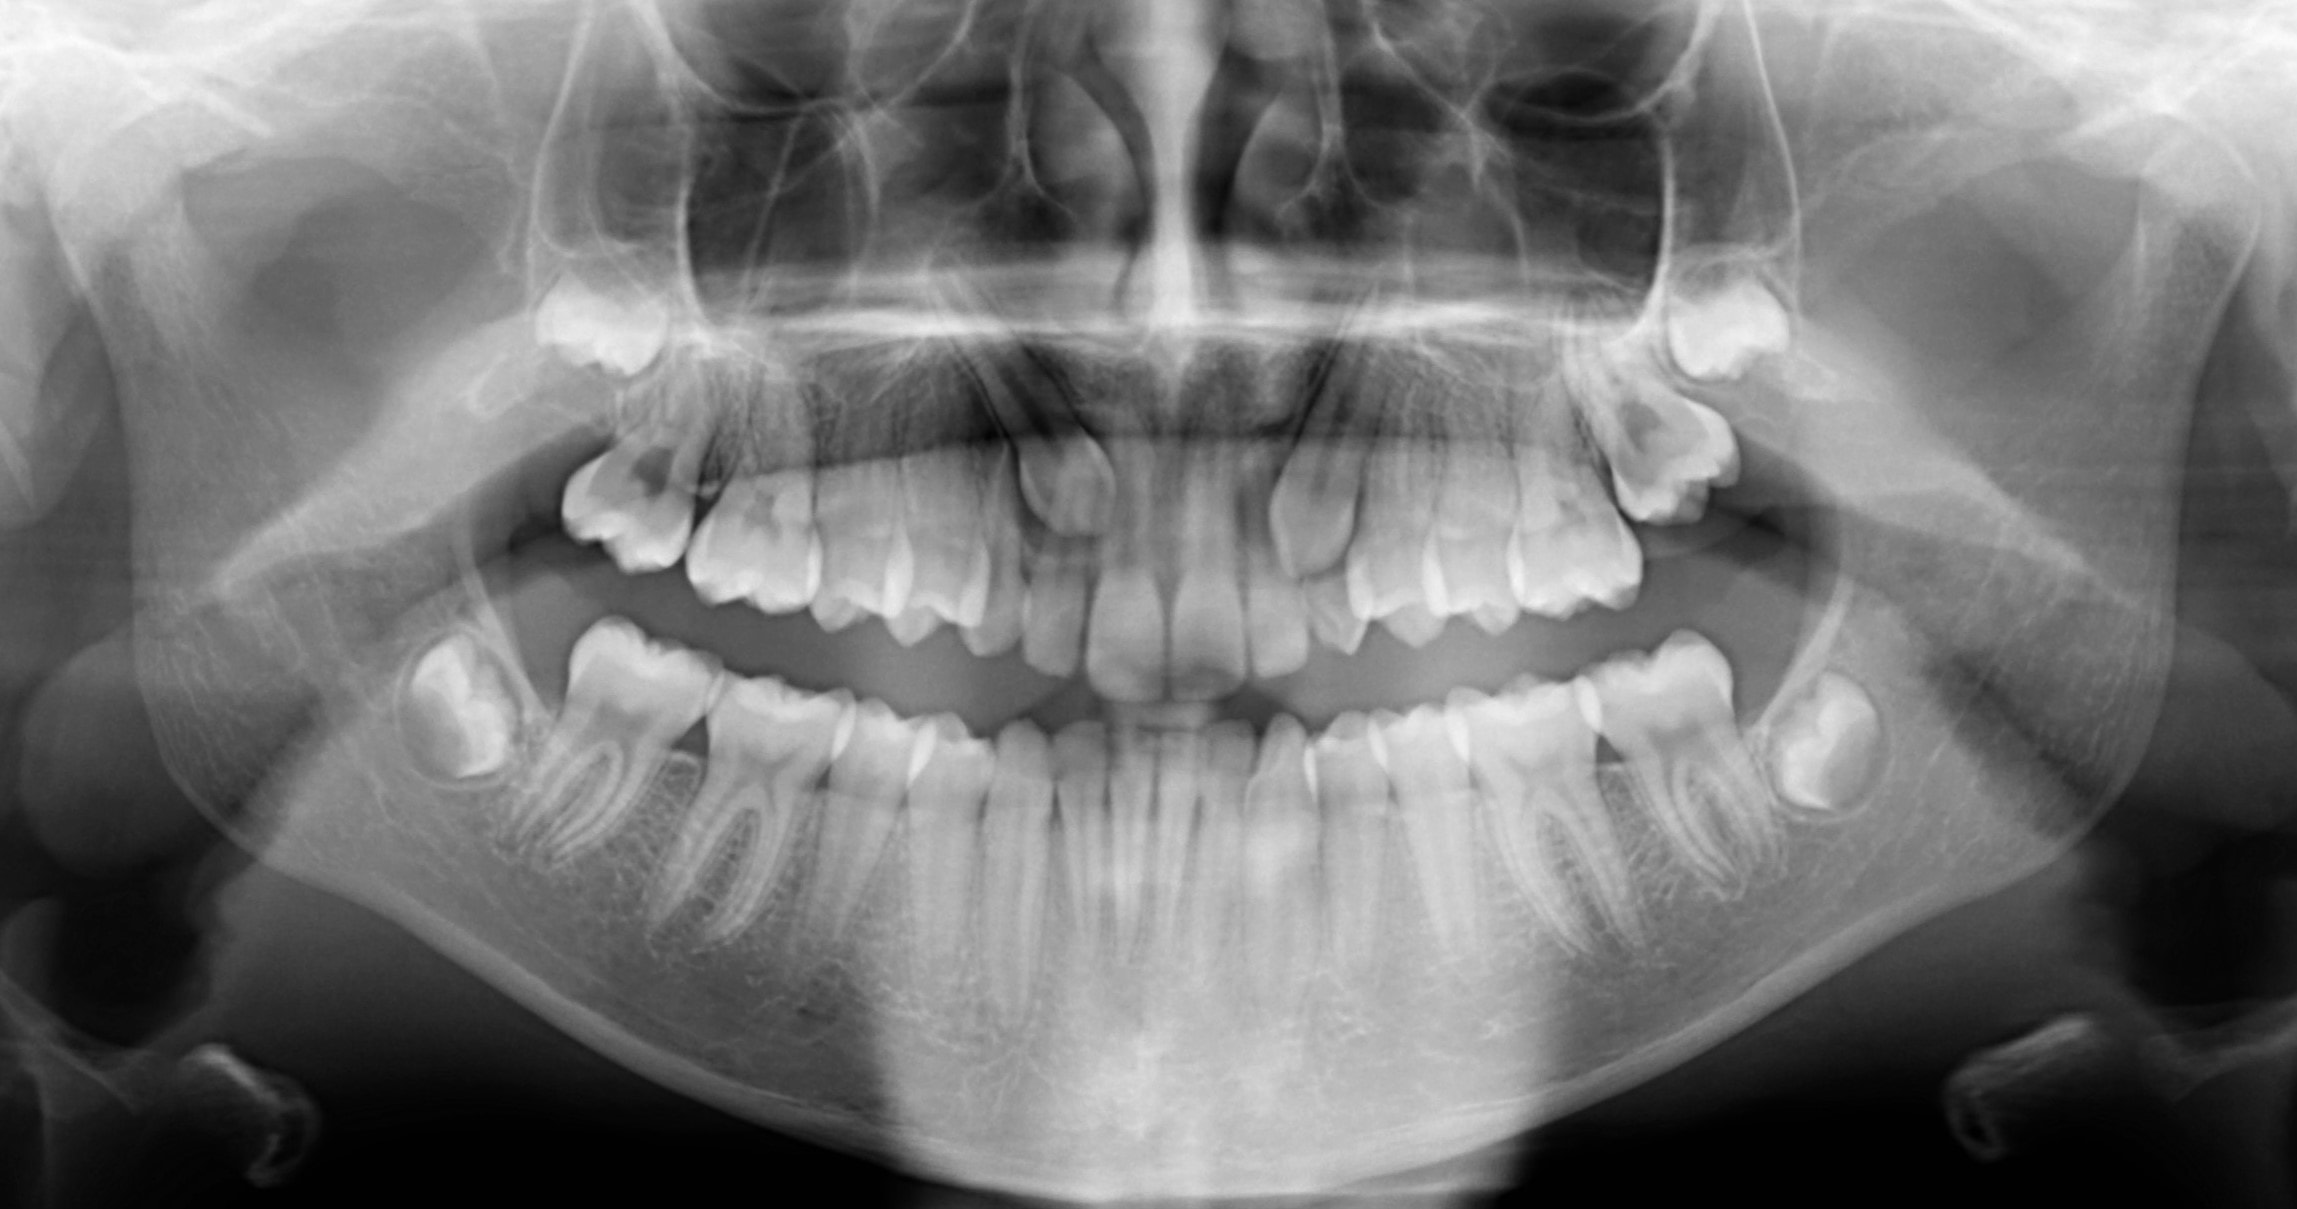

Panoráma röntgen

Panoráma („körbeforgós”) röntgen alatt egy olyan, kétdimenziós felvételt értünk, mely a teljes alsó-felső fogívről megfelelő képet ad, értékelhető rajta az állkapocsízület, valamint az arcüreg is. A foggyökerek és a fogak koronája is jól látható. A röntgen készítése során a röntgenfilm és a röntgensugár a vizsgálni kívánt terület körül forog, egymással szemben elhelyezkedve. Az elülső fogak területére a röntgenkép készítése során sajnos rávetülnek a nyakcsigolyák, így ez a terület kevésbé pontos, éles. Mivel egy körívet egyenesítünk ki, emiatt az oldalsó fogak területe is enyhén torzulhat, nehezebb a kontaktpontoknál keletkező fogszuvasodás felismerése. A panoráma röntgen kiváló diagnosztikus felvétel az általános fogászati állapot megítélése. Sokszor használjuk góckutatás során, hiszen egy röntgenfelvétel készítésével számos területről nyerhetünk diagnosztikus ismeretet. Sugárterhelése minimális.